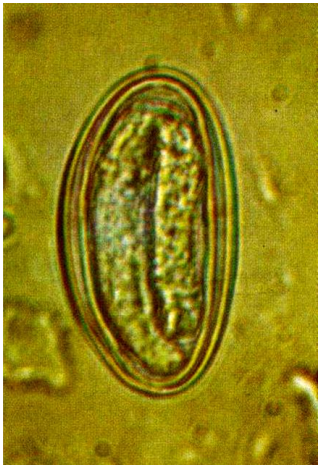

Esse ovo é de ?

Enterobiase